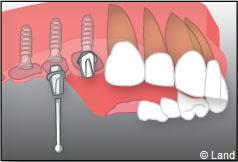

Un implant dentaire est une racine artificielle, placée par le chirurgien-dentiste dans l’os alvéolaire de l’un des maxillaires en remplacement de la racine d’une dent extraite, qui servira de support à une prothèse. Sa forme est généralement cylindrique ou légèrement conique, ressemblant à une vis, en titane ou en zircone, avec une connexion au niveau supérieur, à l’emplacement de la gencive, pour permettre la pose d’un élément prothétique par vissage ou scellement. Son diamètre varie entre 3 et 5 mm et sa longueur entre 8 et 15 mm. La pose d’un implant, réalisée sous anesthésie locale, est totalement indolore. Elle se pratique au cabinet dentaire ou en clinique.

Ensuite il prépare l’emplacement de l’implant dans l’os en passant plusieurs forets de diamètre croissant. Le forage de l’os se fait à vitesse maîtrisée et lente sous irrigation, pour respecter la structure osseuse et éviter tout échauffement de celle-ci. Le praticien arrête lorsqu’il a obtenu un puits d’un diamètre très légèrement inférieur à l’implant à poser.

L’implant est placé dans l’os le plus souvent par vissage et doit avoir une liaison forte avec l’os. Le praticien replace alors la gencive et pose des points de suture.

Exemple d’une réhabilitation complète implantaire